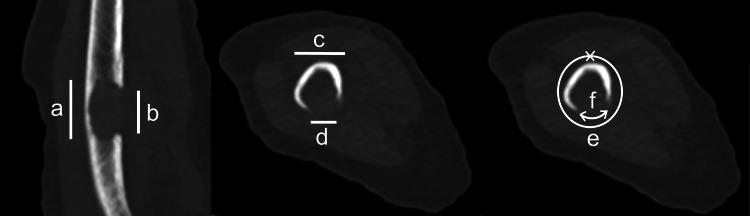

Background Bone metastases often cause pathological fractures and impair patients' quality of life and survival. Although several studies have been conducted on pathological fractures in the femur and spine, limited research has been done on the upper limbs. This study aimed to reveal the risk factors and determine how pathological fractures impact survival in patients with humeral metastasis. Methods This retrospective study was based on patients with humerus metastasis treated in the Nagoya-City University Hospital from 2010 to 2020. Patient characteristics, including sex, age at diagnosis of humeral metastasis, primary cancer, prior treatment, anatomical location, and metastatic lesion size, were retrieved from medical records. The patients were divided into pathological fracture and non-fracture groups, and their backgrounds and survival rates were compared. Results Of the 31 patients with 32 metastatic lesions included in this study, 19 had pathological fractures (one patient had bilateral fractures) and 12 had no fractures. Our analysis revealed that the risk factors for pathological fracture were treatment without bone-modifying agents, treatment without radiotherapy, and larger circumferential cortical involvement. The median overall survival was 21 months; 1-year survival was 56% in the non-fracture group and 59% in the fracture group. There was no significant difference in survival rates between the two groups and only chemotherapy correlated with longer survival in multivariate analysis. Conclusions Bone-modifying agents have the benefit of preventing pathological fractures due to humeral metastases. The humeral pathological fracture did not affect the patient's survival, and chemotherapy was the only prognostic factor that prolonged survival.

背景 骨转移常导致病理性骨折,损害患者的生活质量和生存期。尽管已经针对股骨和脊柱的病理性骨折开展了多项研究,但针对上肢的研究却很有限。本研究旨在揭示肱骨转移患者发生病理性骨折的危险因素,并确定病理性骨折对其生存期的影响。方法 本回顾性研究基于2010年至2020年在名古屋市立大学医院接受治疗的肱骨转移患者。从病历中获取患者特征,包括性别、肱骨转移诊断时的年龄、原发癌、既往治疗、解剖位置和转移灶大小。将患者分为病理性骨折组和非骨折组,比较两组患者的背景情况和生存率。结果 本研究纳入的31例有32处转移灶的患者中,19例发生病理性骨折(1例为双侧骨折),12例未发生骨折。我们的分析显示,病理性骨折的危险因素包括未使用骨改良剂治疗、未接受放疗以及较大范围的皮质周径受累。中位总生存期为21个月;非骨折组1年生存率为56%,骨折组为59%。两组生存率无显著差异,多因素分析中仅化疗与较长生存期相关。结论 骨改良剂有助于预防肱骨转移导致的病理性骨折。肱骨病理性骨折不影响患者生存期,化疗是延长生存期唯一的预后因素。